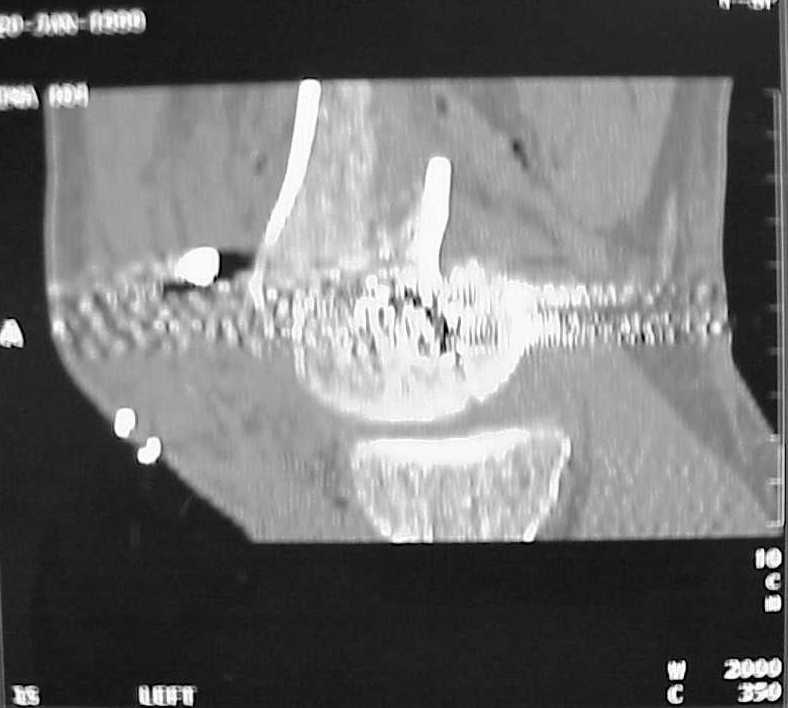

See attached case that was done several years ago before LISS. He had comminuted trochlea and anterior blocking screws were used to prevent anterior IMN cut-out.